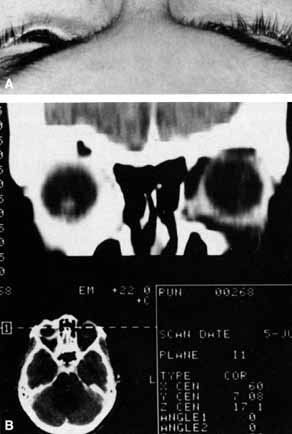

Anosmia caused by damage of cranial nerve I may be a helpful symptom of ethmoid or sphenoid sinus tumors invading the orbit (Fig. 20).44 Olfactory groove meningiomas and esthesioneuroblastomas may also present with anosmia prior to developing vision loss.45 Trauma that involves the orbit and is associated with anosmia should be considered a basilar skull fracture with potential for cerebrospinal fluid leak until proven otherwise (Fig. 21).

Fig. 20 A 13-year-old child presented with a 2-week history of sinusitis and anosmia. Her visual acuity decreased to to 20/400 1 day prior to admission. Computed tomography shows a large ethmoid tumor extending through the cribriform plate and optic canal. A rhabdomyosarcoma was diagnosed by biopsy.

Fig. 21 A 21-year-old man sustained a skull fracture from a motor vehicle accident 2 months prior to this examination. The patient describes anosmia since the accident. Computed tomography discloses a large medial wall orbital fracture extending through the cribriform plate (arrow). Orbital reconstruction was performed through a frontal craniotomy where dura was found incarcerated within the fracture. The orbital fracture was repaired by cranial bone grafting.